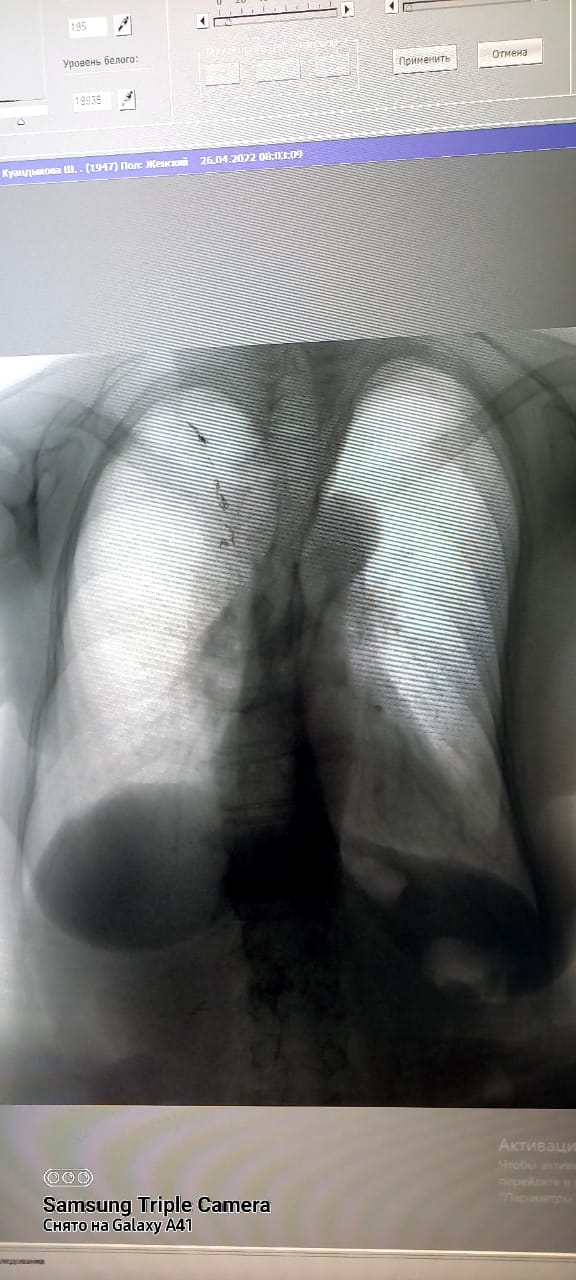

Туберкулез-инфекционное заболевание, возбудитель которого является Мycobacterium tuberculosis. Основной путь передачи туберкулезной инфекции-воздушно-капельный. Основным источником распространения инфекции являются больные туберкулезом легких. Передача заболевания происходит при вдыхании человеком зараженного микобактериями воздуха. Обычно заражение происходит в посещениях. Проветривание и хорошая вентиляция удаляют капельку из воздуха помещения, а прямые солнечные лучи быстро убивают микобактерии туберкулеза. Туберкулез излечим. Для выявления туберкулеза и других заболеваний используется в городской поликлинике №5 имеется новый флюорографический аппарат "ПРОСКАН-2000". Исследования проводятся с 15-летного возроста и старше, и по показаниям флюорография проводится 2 раза в год.